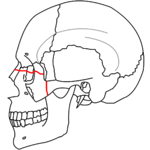

- Le Fort III fracture (transverse), otherwise known as craniofacial dissociation, may follow impact to the nasal bridge or upper maxilla. The salient feature of these fractures, beyond pterygoid plate involvement, is that they invariably involve the zygomatic arch, or cheek bone. These fractures begin at the nasofrontal and frontomaxillary sutures and extend posteriorly along the medial wall of the orbit, through the nasolacrimal groove and ethmoid air cells. The sphenoid is thickened posteriorly, limiting fracture extension into the optic canal. Instead, the fracture continues along the orbital floor and infraorbital fissure, continuing through the lateral orbital wall to the zygomaticofrontal junction and zygomatic arch. Within the nose, the fracture extends through the base of the perpendicular plate of the ethmoid air cells, the vomer, which are both part of the nasal septum. As with the other fractures, it also involves the junction of the pterygoids with the maxillary sinuses. CSF rhinorrhea, or leakage of the nutrient laden fluid that bathes the brain, is more commonly seen with these injuries due to ethmoid air cell disruption, as the air cells are located immediately beneath the skull base.[4]